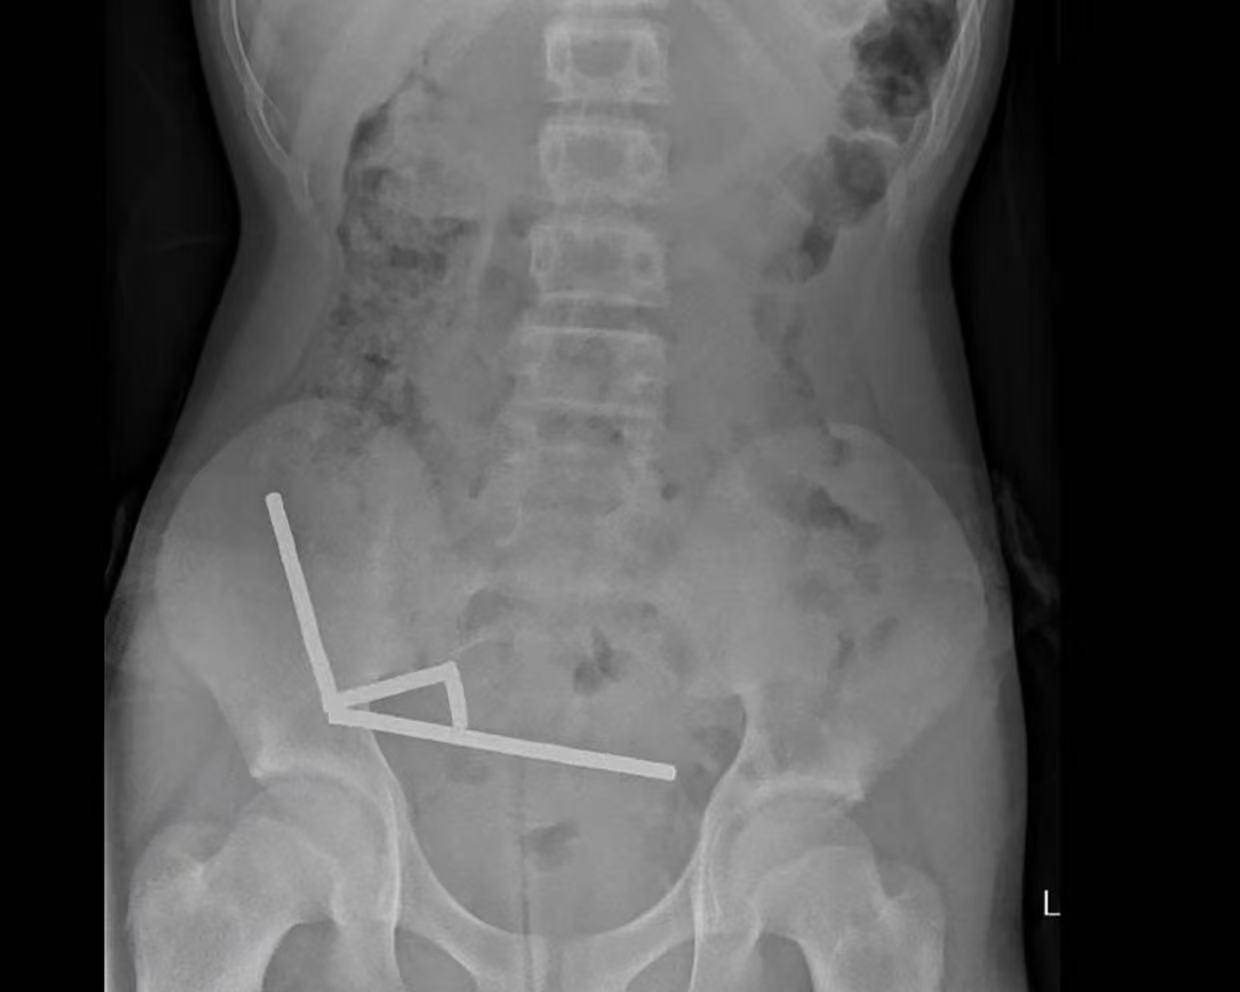

据悉,这名未透露姓名的少年在持续腹痛4天后被送往新西兰北岛的一家医院以太坊app下载。医生通过X光检查发现,这些磁铁在他的肠道内互相吸附,形成了四条链状结构。

▲X光显示以太坊app下载,磁铁在男孩体内紧密吸附成链状结构

据该院医生于周五在《新西兰医学杂志》上发表的报告称,外科医生取出了磁铁并切除了部分受损的肠组织以太坊app下载。磁铁的吸力导致男孩小肠及盲肠(属大肠的一部分)出现四处组织坏死。该男孩在住院8天后康复出院。

医生介绍,男孩大约一周前吞下了80至100颗大功率钕磁铁,每颗尺寸为5×2毫米以太坊app下载。报告称,这些磁铁通过一家跨境电商平台购买。